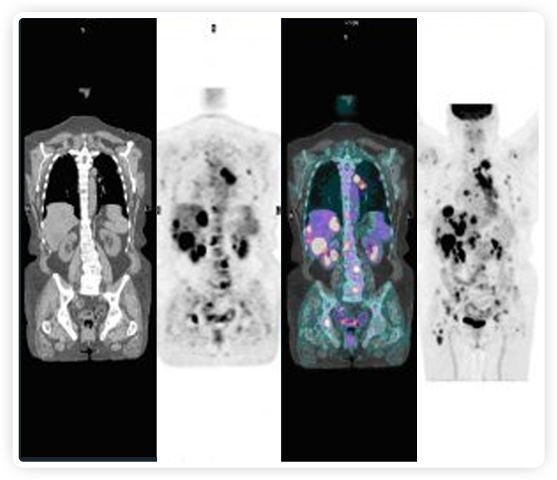

正電子發(fā)射斷層掃描(PET)是癌癥檢測中已建立的成像標(biāo)準(zhǔn),與其他成像方式相比,PET能提供高靈敏度和特異性的圖像。

到目前為止,放射腫瘤學(xué)中(使用的圖像主要是結(jié)構(gòu)性的,而PET圖像可以提供生物學(xué)信息。通過使用注射示蹤劑,例如18-FDG,PET可以描繪腫瘤的代謝活性,使其“點(diǎn)亮”。(FDG是用于可視化癌癥代謝的最廣泛使用的示蹤劑。與正常組織相比,腫瘤細(xì)胞保留更高水平的FDG。)不同的PET示蹤劑可以識別腫瘤的不同生物學(xué)特征,例如特定生物標(biāo)志物抗原(例如,PSMA)或甚至探測免疫系統(tǒng)本身(例如,PDL1表達(dá)或活化的T細(xì)胞)。